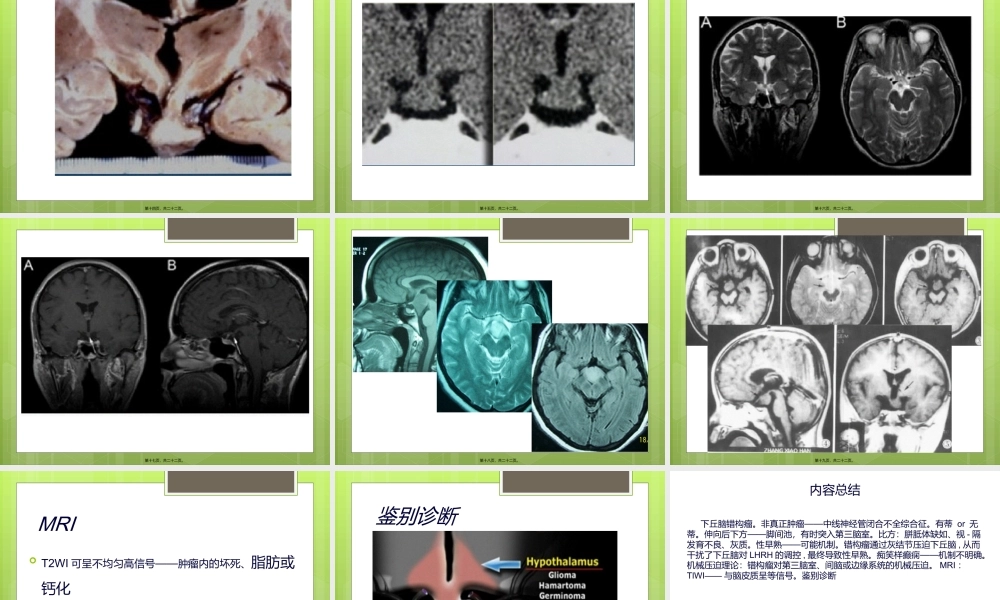

下丘脑错构瘤北京大学第一医院北京大学第一医院第一页,共二十二页。组织分类WHO1993年对中枢神经系统肿瘤的组织分类:囊肿及肿瘤样病变少见的先天性脑畸形第二页,共二十二页。病因非真正肿瘤——中线神经管闭合不全综合征约发生于妊娠期第5-6周由正常脑组织形成的异常肿块第三页,共二十二页。起源起源于灰结节和乳头体有蒂or无蒂伸向后下方——脚间池,有时突入第三脑室偶可位于视交叉前,或游离于脚间池内第四页,共二十二页。第五页,共二十二页。第六页,共二十二页。单独存在伴单个或多个脑外先天性畸形比方:胼胝体缺如、视-隔发育不良、灰质异位、微小脑回畸形、大脑半球发育不良、多指、面部畸形、心脏缺陷等第七页,共二十二页。流行病学常见于婴幼儿和儿童发病年龄常<3岁但局部可于成年后发病男女发病率无显著差异〔女略多于男〕第八页,共二十二页。临床表现——特征性性早熟痴笑样癫痫可伴其他类型癫痫或行为异常、智力障碍及尿崩症等第九页,共二十二页。性早熟——可能机制下丘脑错构瘤中的一些神经元含有促性腺激素释放激素分泌颗粒错构瘤通过灰结节压迫下丘脑,从而干扰了下丘脑对LHRH的调控,最终导致性早熟异常神经元连接第十页,共二十二页。痴笑样癫痫——机制不明确机械压迫理论:错构瘤对第三脑室、间脑或边缘系统的机械压迫电生理理论:错构瘤神经元的癫痫样放电神经内分泌理论:错构瘤分泌致癫痫的神经肽第十一页,共二十二页。MRI首选检查区分肿瘤及其周围重要组织结构的解剖关系为制定手术方案、评估手术风险、判断预后第十二页,共二十二页。典型影像学表现位于中线灰结节、乳头体处的均质球形肿块边缘清楚CT:与脑皮质等密度肿块MRI:TlWI——与脑皮质呈等信号T2WI——等、稍高、高信号第十三页,共二十二页。第十四页,共二十二页。第十五页,共二十二页。第十六页,共二十二页。第十七页,共二十二页。第十八页,共二十二页。第十九页,共二十二页。MRIT2WI可呈不均匀高信号——肿瘤内的坏死、脂肪或钙化CT、MRI肿块无强化——下丘脑错构瘤是异位神经组织第二十页,共二十二页。鉴别诊断第二十一页,共二十二页。内容总结下丘脑错构瘤。非真正肿瘤——中线神经管闭合不全综合征。有蒂or无蒂。伸向后下方——脚间池,有时突入第三脑室。比方:胼胝体缺如、视-隔发育不良、灰质。性早熟——可能机制。错构瘤通过灰结节压迫下丘脑,从而干扰...

0下载

1下载